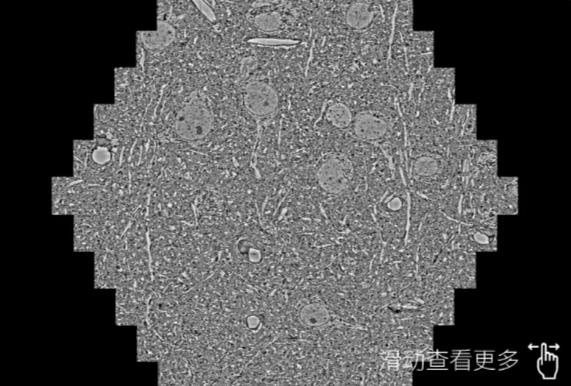

鼠脑切片。左图使用烟台蔡司烟台扫描电镜MultiSEM706对165μmx143pm面积区域成像,耗时仅需1.5秒。右图为鼠脑切片中30μm区域放大效果。样品由芝加哥大学B.Kasthuri提供。

使用蔡司高速烟台扫描电镜MultiSEM对1mm²人脑皮层组织进行高分辨成像,并对其中的各种细胞结构进行三维重构分析。左图展示了2x3mm²组织平面中锥体神经元的三维重构效果。右图显示了局部体积神经元三维重构。图像由哈佛大学chtman实验室提供,渲染图由D. Berger 制作。